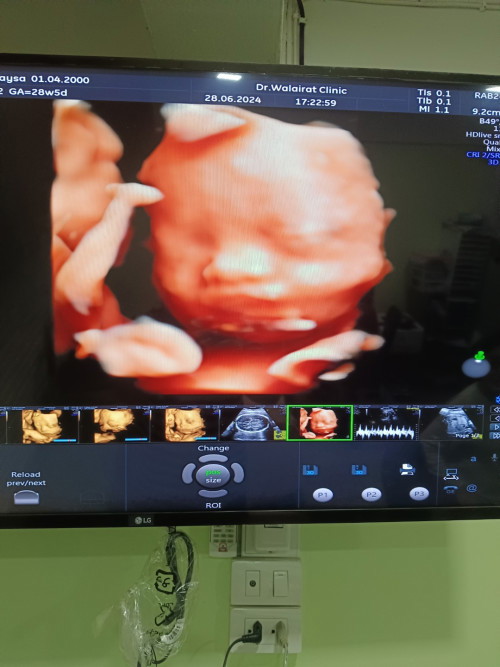

วันนี้ไปตร้าซาวมา คุณหมอบอกน้องกลับหัวแล้ว น้ำหนัก1600กรัม น้ำหนักแม่ขึ้นมาทั้งหมด5โลค่ะ ในภาพน้องเอามือปิดแก้มนะคะ